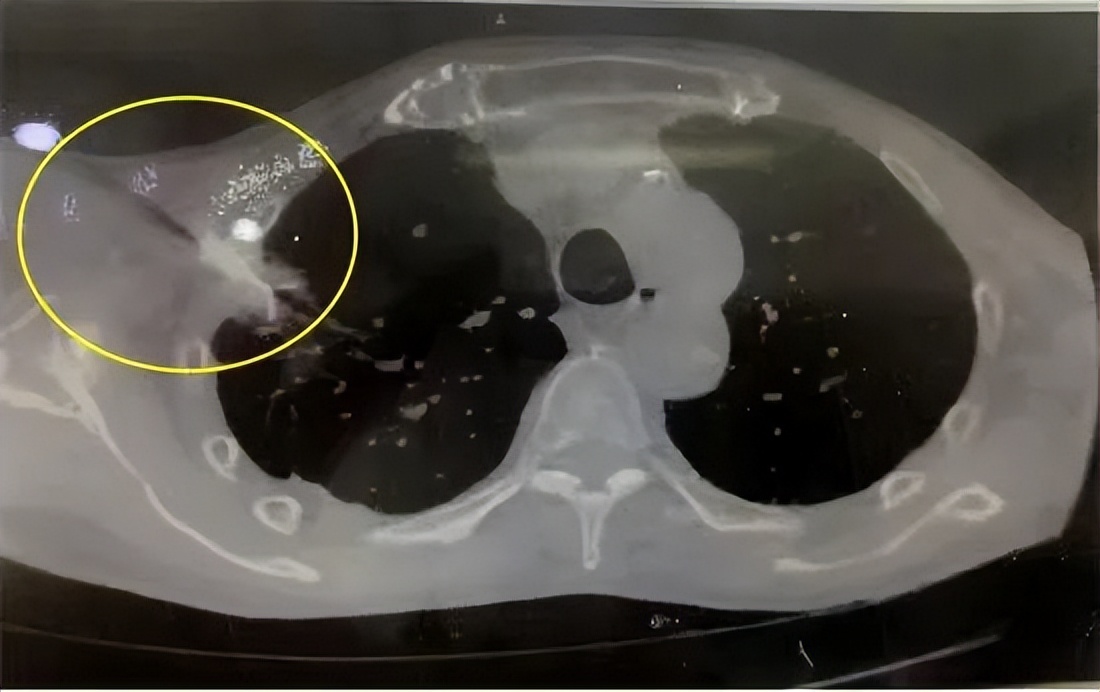

患者右上肺小肺癌,本身年龄大、身体情况差,拒绝手术治疗。

CT引导下射频针插入右上肺癌,高温消融灭活肿瘤。

半年后复查,肺癌灭活基本吸收消失。